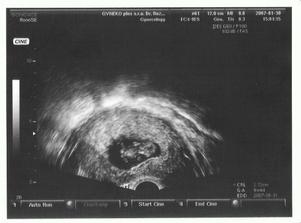

SRPŇÁTKA 2007 - fotky UTZ

album věnované mimískům, které se narodí v srpnu 2007 a jejich maminkám ze "Společného termínu SRPEN"